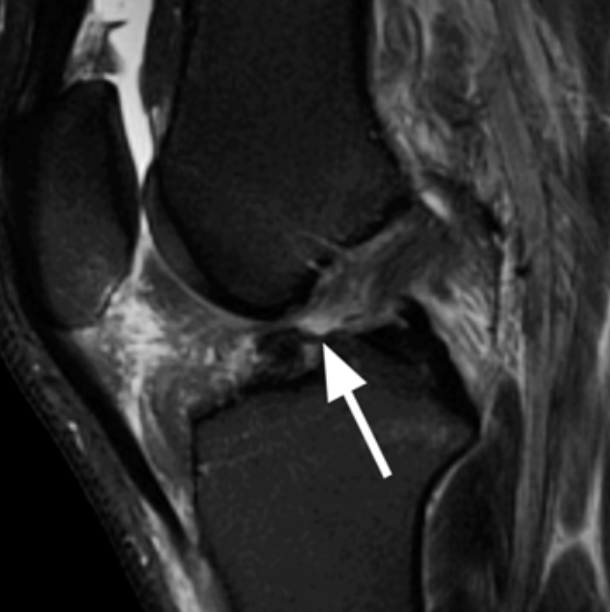

(2)MRI:对诊断膝关节前交叉韧带断裂非常有价值,表现为韧带缺失、连续性中断、走向改变、信号改变。